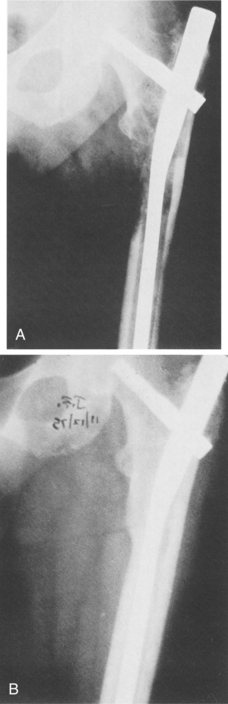

Because osteosarcoma is relatively resistant to radiation therapy, complete surgical removal of the primary tumor and any metastases is essential to cure.6 The current surgical thinking is to use limb-sparing techniques (segmental resection and replacement with bone graft or implant) whenever possible (Fig. 26-8).

Figure 26-8 Osteosarcoma of the distal femur in a 17-year-old boy. A, Intraoperative photograph following resection of the distal femur. B, Postoperative radiograph of custom-made, rotating-hinge prosthesis. C, Follow-up clinical photograph (3 years after surgery). Soft tissue coverage of the prosthesis by latissimus dorsi myocutaneous free flap with acceptable cosmesis. (From Klein M, Kenan S, Lenis M: Osteosarcoma: clinical and pathologic considerations, Orthop Clin 20:343, 1989.)

The tibia turn-up is another important procedure that is an option in cases of osteosarcoma (Fig. 26-10). The leg is amputated above the knee, and the tibia bone from the lower leg is inverted, or turned up, making it possible for the ankle end of the tibia to be fused to the bottom of the femur. The muscles are then sutured back onto the tibia.19,20

Figure 26-10 Tibia turn-up procedure. Sarcoma just below lesser trochanter in a 7-year old girl. There were three surgical options for this client: (1) transtrochanteric amputation (major loss of limb), (2) tibia turn-up procedure (shown here), or (3) rotationplasty (see Fig. 26-9). The tibia turn-up procedure was chosen for cosmetic reasons with excellent functional outcomes with the use of a prosthesis. The tibia turn-up procedure avoids high-level transfemoral amputation and provides an outcome similar to that of a knee disarticulation amputation. (Courtesy Kevin Carroll, Hanger Prosthetics and Orthotics, Orlando, FL.)

Tibia turn-up is an alternative that people may consider when the appearance of a rotationplasty seems too extreme. Tibia turn-up is also an option when cancer occurs in the thigh that might otherwise require a high-level above-knee amputation (Fig. 26-11). By having the tibia fused to the femur, these individuals now have a long residual limb that will be easier to fit with a prosthesis, providing them with increased function. Although these individuals will wear an above-knee prosthesis with a mechanical knee, their comfort and mobility will usually exceed that of above-knee prosthesis users with a short residual limb.19